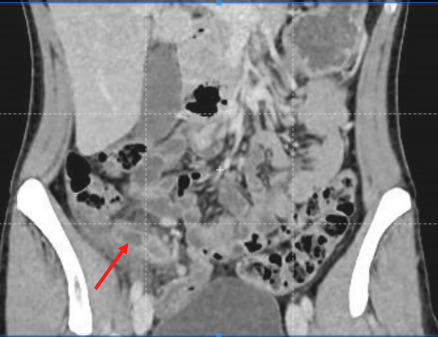

Scanner abdominopelvien injecté : la référence

Le scanner abdominopelvien avec injection intraveineuse de produit de contraste est l’examen de référence, avec une excellente performance diagnostique. Il permet, dans le même temps, d’éliminer de nombreux diag­nostics différentiels et détermine la présence ou non d’une complication de l’appendicite, telle qu’un abcès ou une péritonite. Le diagnostic ­positif repose sur une augmentation du diamètre de l’appendice, une infiltration de la graisse périappendiculaire, un épaississement et une prise de contraste de ses parois (fig. 2).